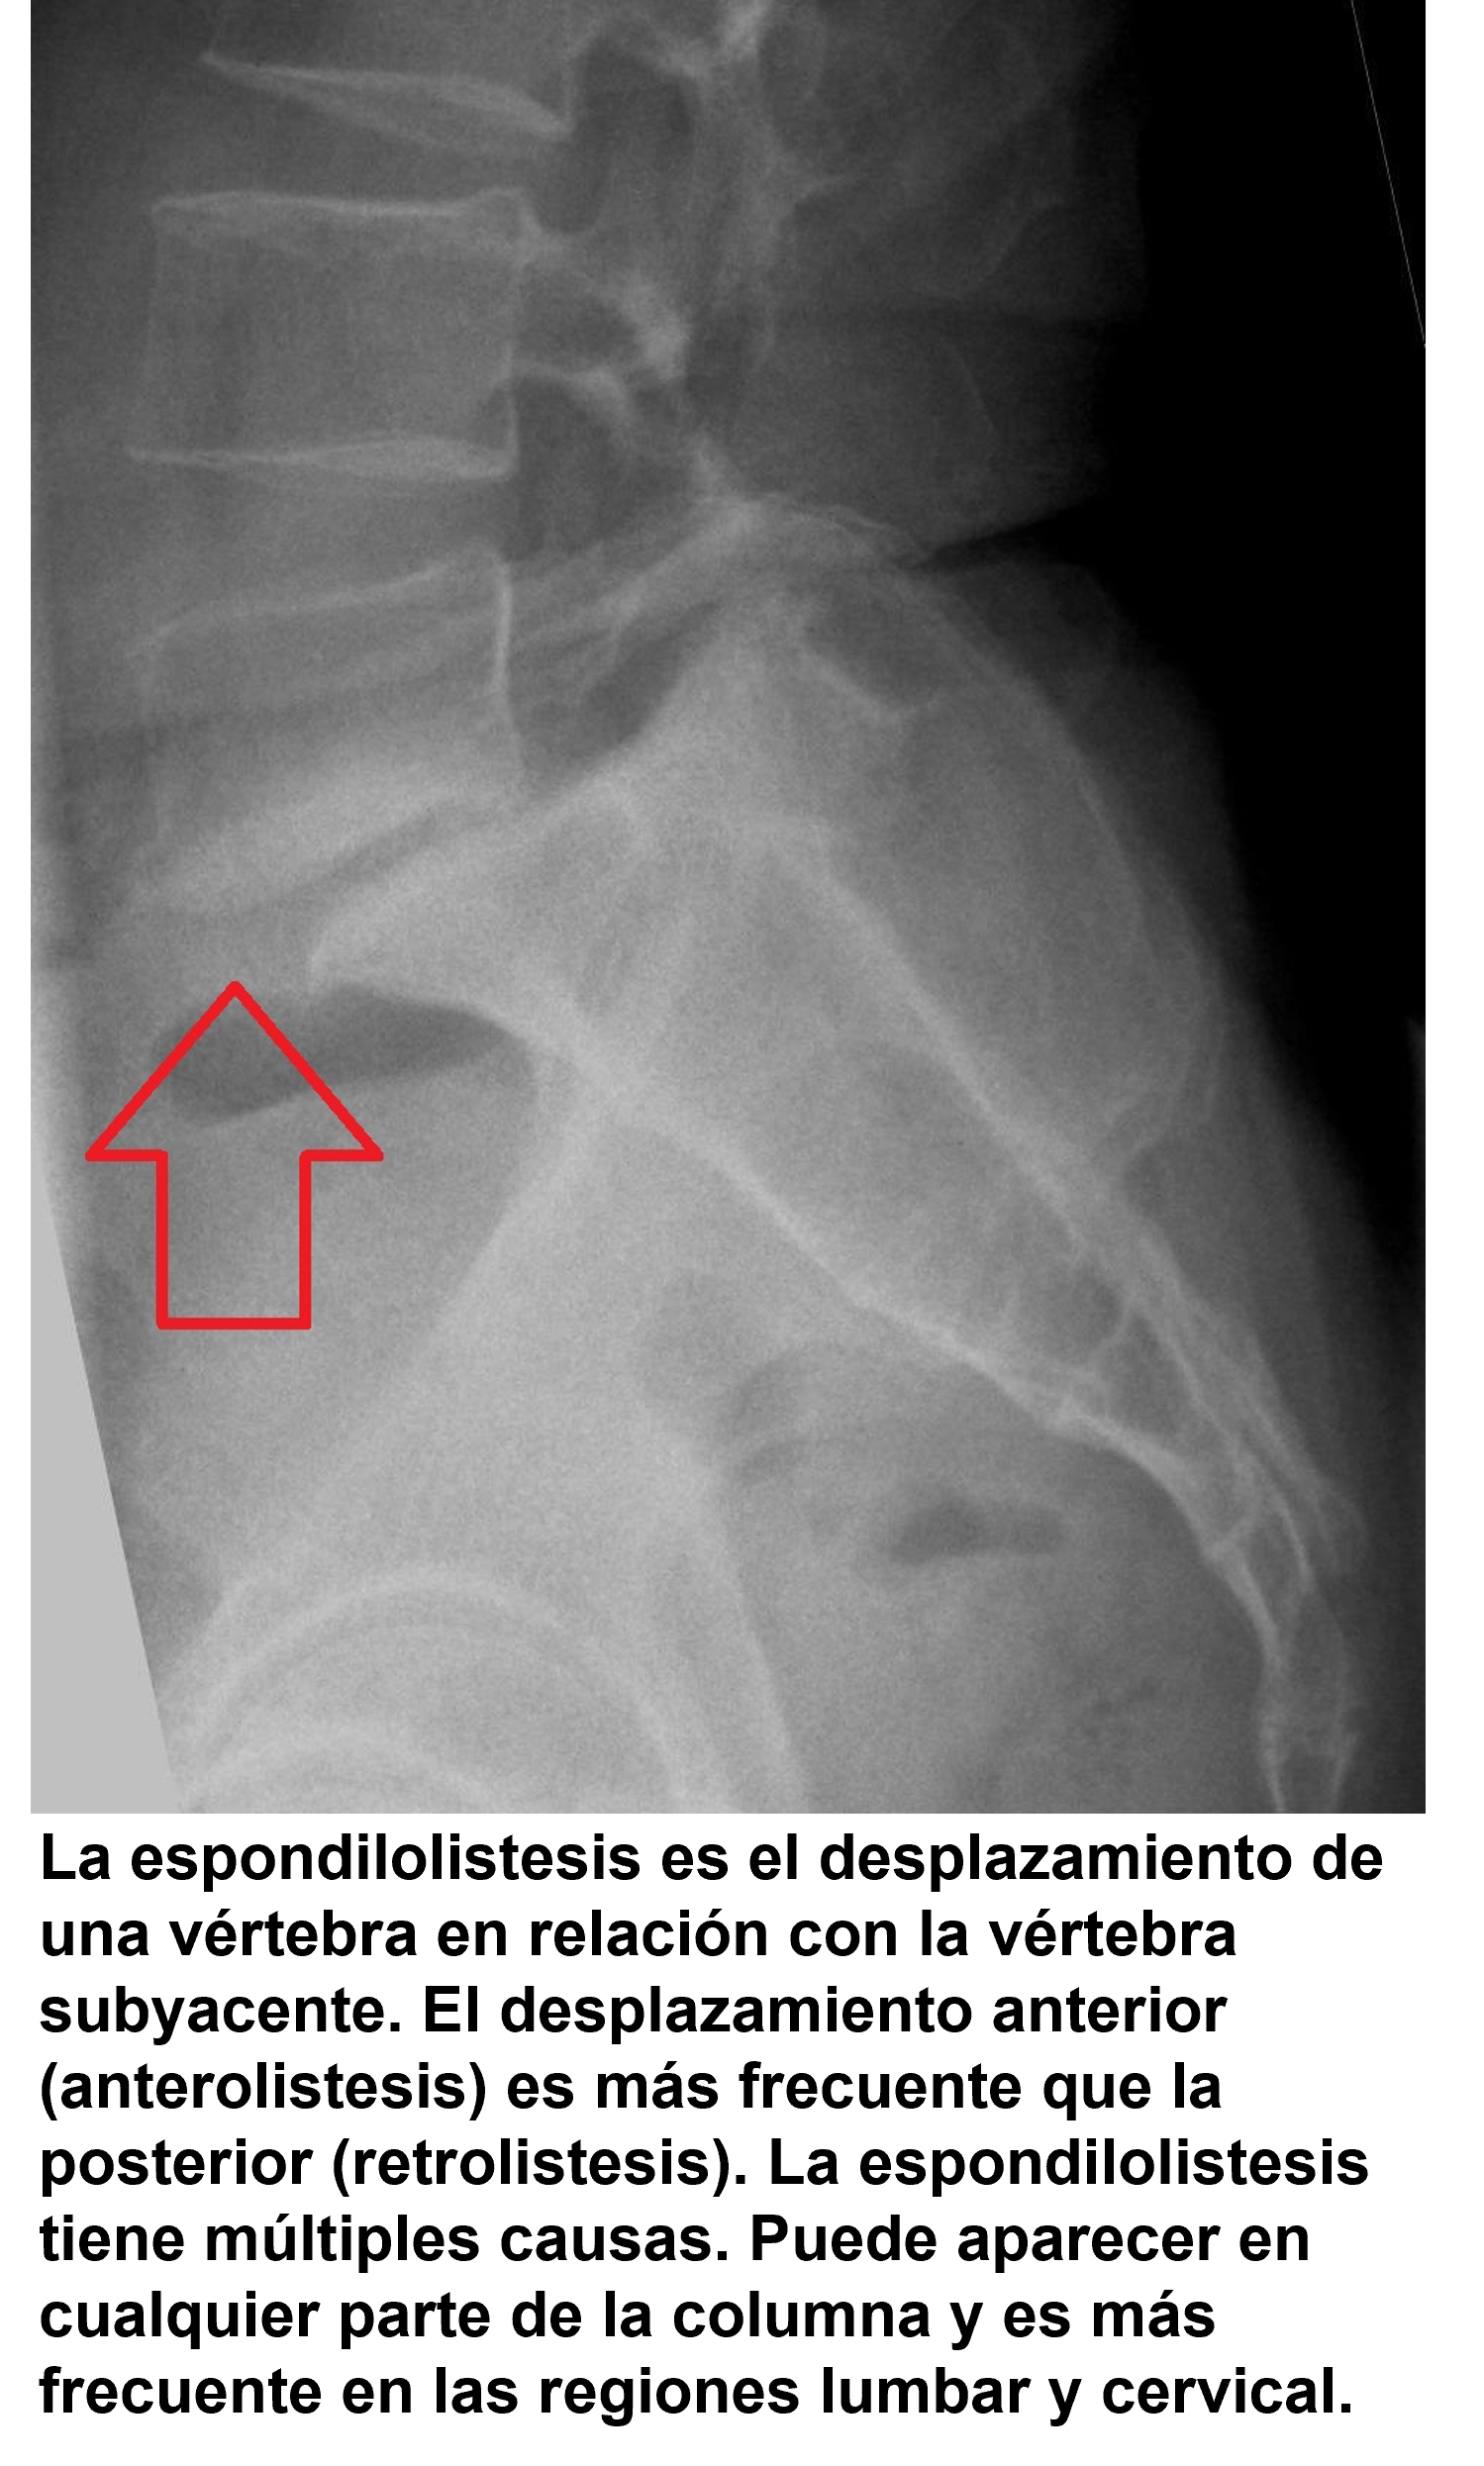

- Estenosis del canal lumbar. Espondilolisis y espondilolistesis.